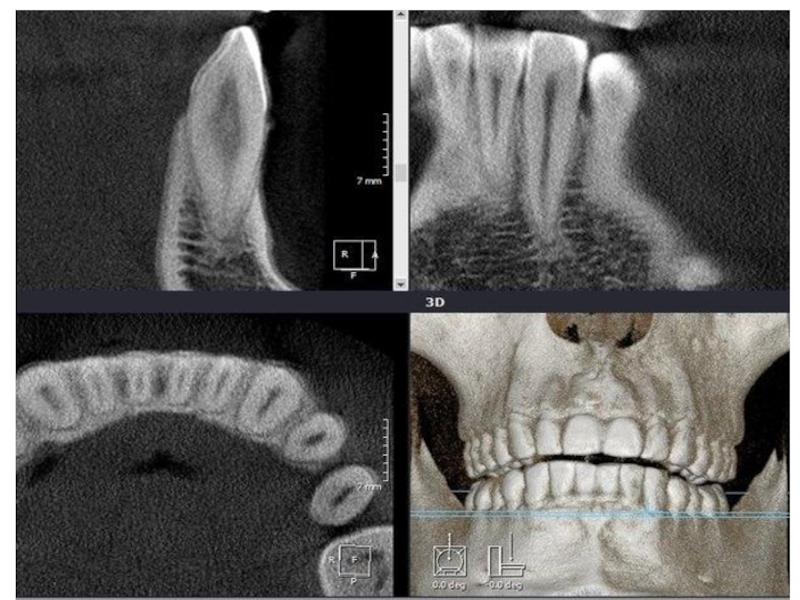

Слайд 7Ренгенологиялық зерттеуде жылжыған тістің периодонтальды саңылаудың кеңеюі, оның деформациясы, тіс альвеоласының

атрофиясы, тістің қисайған бағытында сүйектің қалатаны байқаймыз. Тіс түбірінің ұшында остеопороз шекарасын туындайды, оны кейде созылмалы периодонтит ошағымен шатастырады.

Слайд 17Рентгеналогиялық зерттеу